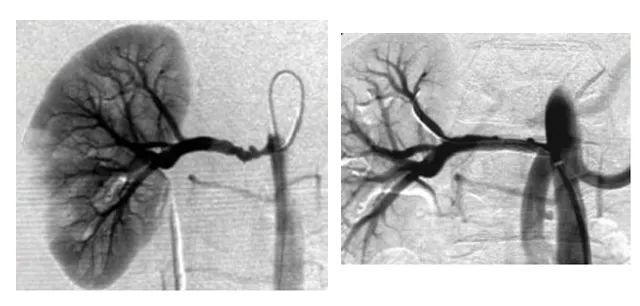

近年来介入治疗因其微创优势为越来越多的病患所接受。成人快手 领导高度重视介入学科的发展。经过一年紧张的筹备,成人快手 介入室建设工作已进入尾声,成人快手 外科一病区(血管瘤和脉管畸形病区)又新添先进诊疗“利器”——大型数字化平板血管造影机(DSA),该设备的引进将进一步帮助外一病区“无死角”开展血管瘤与血管畸形以及常见外周血管疾病的介入治疗。

介入治疗的定义:在医学影像学设备引导下利用特殊器材进入人体,对疾病进行治疗和诊断的一门新兴学科。其特点是微创、高效、可重复性强、副作用和并发症相对较轻。技术优势是无孔不入,无孔也入,几乎可以达到人体各个器官、管道和腔隙。介入医学根据介入(进入)到病灶的途径不同,可分为经血管介入(导管介入)及经非血管介入(直接穿刺病灶)两种。血管性介入:是指在DSA引导下通过穿刺动脉或静脉,引入导丝、导管至病变靶部位,在血管内进行局部微创治疗的方法。非血管介入:是指在CT、B或MRI引导下经皮穿刺至病变靶部位,进行局部微创治疗的方法。基本操作技术概括起来包括:“灌、通、堵、取”及其它等技术。

成人快手 外一科目前开展血管瘤与血管畸形的诊疗工作,诊因其血液供应丰富,传统手术切除往往达不到理想的治疗效果,单纯切除病灶较困难,术后复发风险较高。经血管的介入治疗属于微创手术,可以减少术中出血,术后恢复较快。介入治疗时可以精准定位畸形血管团,做到有针对性的栓塞与治疗,治疗成功率较高、并发症较少,效果显著。